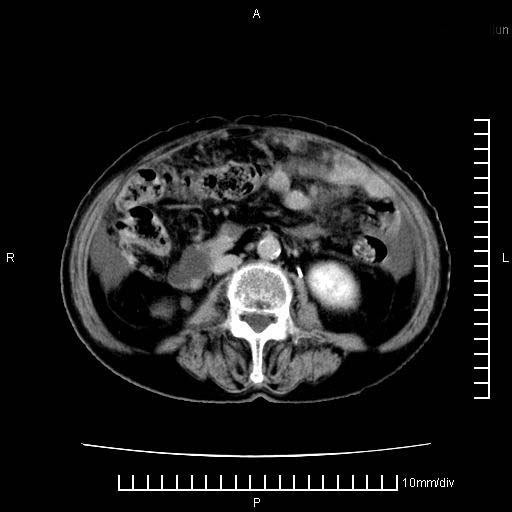

标题: CT28280:腹部增强:女性,80岁

上腹疼痛月余,外院核磁诊断胰腺癌。现临床示右下腹可明显触及包块,可片子上怎么没有看到?

1.胰腺颈体部癌。

2。腹腔积液。

胰腺体部癌累及周围器官,腹膜、粘连

胰腺结构模糊,胰尾部见囊性包块,周围脂肪密度增高,左肾前筋膜增厚,胸水、腹水。不符合胰腺ca伴腹膜腔转移。考虑胰腺炎伴假性囊肿形成、胸腹腔积液。

1)考虑胰腺癌并胰腺假性囊肿形成。2)肝内低密度灶,不排除转移。3)右肾盂积水。4)腹水。5)右侧胸腔积液并右肺下叶部分膨胀不全。